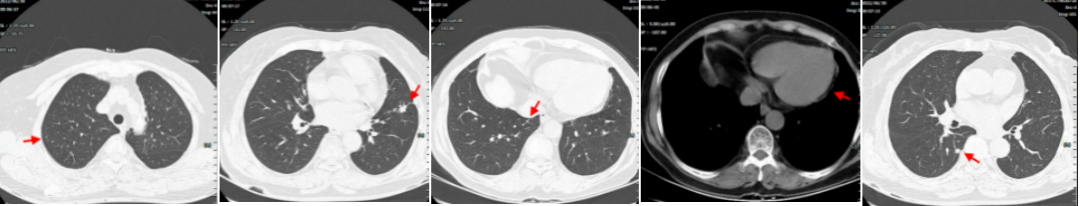

病例简介 该病例是一个肺腺癌(cT4N0M1a)IVa期患者,合并有高血压、冠心病、糖尿病。一线治疗前基因检测结果提示EGFR 19del(+)。一线治疗(埃克替尼片125mg tid)疗效评估为PR、PFS 22个月。一线治疗前基因检测结果提示EGFR 19Del(+)、T790M(+)。后入组D0316(贝福替尼)在EGFR阳性局部晚期或转移性非小细胞肺癌的II期临床试验(IBIO-102项目)。治疗先后由D0316 75mg qd更改方案为D0316 100mg qd,疗效评估为PR,、PFS>32月。至今患者仍持续用药随访中。 Part 1 基本信息 患者:女性;74岁。 主述:反复咳嗽3年,加重伴呼吸费力4月,于2018-1-17就诊。 既往史: 高血压病史10年,服用络活喜、厄贝沙坦氢氯噻嗪、美托洛尔控制血压;冠心病,冠脉支架置入术后4年;糖尿病史2年;否认其他病史。 Part 2 诊疗经过 治疗前辅助检查 2018-1-17查体:血压129/85mmHg;无明显阳性体征。 实验室检查 2018-1-18:血CEA 9.9ng/ml、Cyfra21-1 4.3ng/ml;SCC、NSE、Pro-grp均正常;血常规(Hb 109g/l)、肝肾功能、crp正常。 影像学检查 2018-1-8胸部CT:两肺多发结节,考虑MT伴转移,对照2017-10-4片增大,冠脉钙化,左侧部分肋骨陈旧性骨折,胆囊结石; 2018-1-22腹部B超:脂肪肝倾向,胆囊结石,两肾囊肿,两侧肾上腺未见明显异常回声; 2018-1-21头颅MRI:平扫+增强未见明显异常; 2018-1-23骨ECT:全身骨显像未见明显转移征象。 治疗前病理诊断 肺腺癌(cT4N0M1a) IVa期; 2018-1-18肺穿刺及病理:CK7( ++++ );NapsinA( ++++ ) ;TIF-1(++++);EGFR 19Del(+) ;ALK(-) 。 治疗前临床诊断 肺腺癌(cT4N0M1a) IVa期;PS 1分;EGFR 19Del(+);冠心病、冠脉支架置入术后;高血压病;糖尿病。 一线治疗 治疗方案:2018-1-26开始,埃克替尼片125mg tid。 疗效评估(PR,PFS 22月 ) 埃克替尼治疗11.3个月,两肺结节减少、缩小,达到PR (2018-12-4);治疗22个月,左下肺结节增大、肺内新发小结节、新发心包积液,出现PD(2019-11-21)。 2018-1-18 治疗前基线 2018-12-4 埃克替尼 11.3月(PR) 2019-11-21 埃克替尼 22月(PD) 一线治疗后辅助检查 实验室检查 2019-11-29血CEA 8.4ng/ml ;Cyfra21-1 4.8ng/ml;SCC、NSE、Pro-grp均正常。 2019-12-13血生化肌酐84umol/l;肝功能正常;血常规正常。 影像学检查 2019-12-4头颅MRI平扫+增强:脑内少许腔梗灶; 2019-12-2骨ECT:全身骨显像未见明显转移征象; 2019-12-4腹部增强CT:胆囊结石,右肾上腺及胰腺钙化灶,两肾囊肿。 生理学检查 2019-12-13 ECG:窦性心律,T波改变; 2019-12-13心超:左室轻度增大,左室壁偏厚,左房轻度增大,轻度肺动脉高压伴轻度三尖瓣返流,心包积液,脏层心包增厚,左室舒张功能轻度减退。 一线治疗后病理诊断 2019-11-29分子病理(ARMS法):EGFR 19Del(+) ;T790M(+)。 临床诊断 肺腺癌(cT4N0M1a);IVa期;肺、心包转移;PS 1分;EGFR 19Del(+);T790M(+);冠心病;冠脉支架置入术后;高血压病;糖尿病;肾功能不全。 二线治疗 入组D0316(贝福替尼)在EGFR阳性局部晚期或转移性非小细胞肺癌的II期临床试验(IBIO-102项目)。 治疗方案 2019-12-19开始D0316 75mg qd,于2019-12-24至2020-1-15出现头痛、肩背痛1级AE,自行缓解; 2020-1-13开始D0316 100mg qd; 合并用药有针对糖尿病药物西格列汀片 50mg qd;针对高血压药物氨氯地平5mg qd、厄贝沙坦氢氯噻嗪片1片qd、美托洛尔缓释片47.5mg qd;针对冠心病药物西洛他唑 50mg bid;针对睡眠障碍药物氯硝西泮片1mg qn、艾司酉酞普兰片10mg qd、喹硫平片50mg qd。 安全性评估 疗效评估(PR, PFS>32月 ) D0316 治疗6周就达到PR,患者左下肺靶病灶缩小,两肺小结节稳定、部分缩小(2020-1-28);治疗30周仍为PR,且心包积液减少(2020-7-13);治疗30.5月仍为PR,右下叶背段胸膜下结节缓慢进展(2022-6-30)。 2019-11-21 D0316 治疗前基线 2020-1-28 D0316 治疗6周(PR) 2020-7-13 D0316 治疗30周(PR) 2022-6-30 D0316 治疗30.5月(PR) 2022-6-30腹部增强CT:胆囊结石,右肾上腺及胰腺钙化灶,两肾囊肿。 目前D0316(贝福替尼) 100mg qd 治疗中, PS 1分。